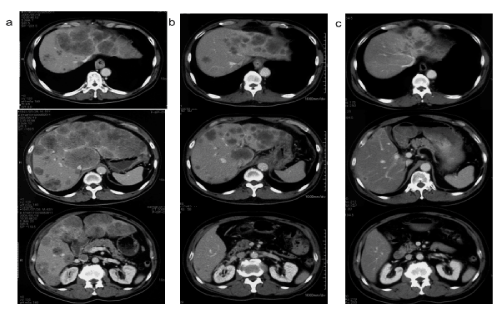

Figure 3. Abdominal contrast-enhanced CT scan

a) Before the start of treatment, multiple metastatic lesions on both sides of the liver are present. Note that there is significant enlargement of the liver and thickening of the oesophageal wall, which is where the primary lesion was located

b) Day 27 of the disease: the tumour shrunk and the liver enlargement was reduced

c) Day 179 of disease: further shrinkage of the tumour

The upper gastrointestinal endoscopy identified a type 2 tumour in the lower thoracic oesophagus (Figure 1). The biopsy-based diagnosis according to the patient’s previous physician was low to moderately differentiated squamous cell carcinoma (Figure 2). An oesophageal ultrasonic endoscopy did not find any evidence of infiltration in the aorta. A contrast-enhanced, chest computed tomography (CT) scan found no evidence of regional lymph node metastasis (Figure 3a). However, both large and small nodular shadows were observed in both lobes of the liver. The S1 mass excluded the inferior vena cava.

After obtaining informed consent from the patient, low-dose nedaplatin plus 5-FU therapy (nedaplatin at 10 mg/body/day IV(intravenous drip) d1–5, 8–2, and 15–19; 5-FU at 500 mg/body/day CIV d1–5, 8–12, and 15–19; total regimen repeated every 4 weeks) [9,10], as well as simultaneous palliative radiation therapy at 40 Gy of total dose, delivered in 20 fractions, was initiated. After the start of treatment, the blood biochemistry examination on day 15 of the disease tended to improve, as shown in figure 4, and the CT scan taken on day 27 (Figure 3b) revealed a partial response (PR) to treatment. Even though the patient was scheduled to start the second course of treatment on day 29, this was interrupted due to the development of a grade 2 decline in platelet counts (56,000/μL). Upon resuming treatment, the patient requested a shortened hospitalization period and refused the administration of anticancer drugs on consecutive days. For this reason, the patient was switched to a nedaplatin plus 5-FU therapy regimen (nedaplatin at 50 mg/m2 IV d1; 5-FU at 500 mg/m2 CIV d1–5, repeated every 2 to 3 weeks) [10], beginning on day 49, and the patient was discharged on day 56. Using an infuser pump during outpatient visits, the patient underwent a total of 7 courses of the new chemotherapy regimen by day 245. The CT scan taken on day 179 showed the largest treatment effect (Figure 3c), with the original liver enlargement almost completely gone with normal biochemical test findings (Figure 4). Despite maintaining a PR thereafter, we identified the re-enlargement of the metastatic liver tumours according to a CT scan on day 255. Therefore, the patient was switched to 2 courses of docetaxel plus cisplatin therapy (docetaxel at 60 mg/m2 d1; cisplatin at 60 mg/m2 d1; repeated every 3 to 4 weeks) [11], as the tertiary treatment after the determination of progressive disease (PD). A CT scan on day 308 revealed tumour shrinkage and resulted in a determination of PR, but due to general malaise, loss of appetite, and a refusal to undergo in-patient treatment, the patient was switched to 4 courses of docetaxel monotherapy (docetaxel at 70 mg/m2 d1; repeated every 3 weeks) [12] as a quaternary treatment. However, due to the determination of PD by a CT scan performed on day 394, the patient was switched to 5 courses of outpatient vindesine plus nedaplatin chemotherapy (vindesine at 3 mg/m2 d1 and d8; nedaplatin at 90 mg/m2 d1; repeated every 4 weeks) [13] beginning on day 399 as a quinary treatment. However, the patient died on day 611, following rapid enlargement of the liver tumours and cancerous peritonitis. With respect to the primary lesion, the patient had shown a complete response (CR), according to an upper gastrointestinal endoscopy performed on day 76 and had maintained CR, even on an endoscopy examination performed on day 405 (Figure 1b). In addition, the patient was able to consume food orally until right before death.